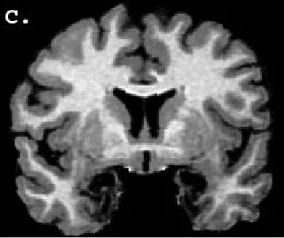

Amerika'nın Kentucky eyaletinde yaşayan bir kadın, beyninin Amigala kısmında yer alan genetik bir bozukluk nedeniyle korku duygusuna sahip değil.

İlk olarak 1994 yılında tıp literatürüne giren bu rahatsızlığın genel ismi Urbach-Wiethe.